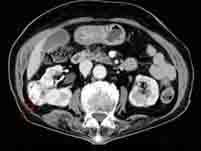

诊断肾肿块最好的检查方法是()A.B超B.CTC.IVUD.腹平片E.肾图

问题 诊断肾肿块最好的检查方法是()

选项 A.B超 B.CT C.IVU D.腹平片 E.肾图

答案 B